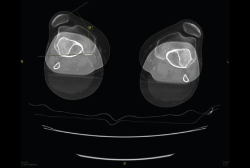

5.1. TA-GT (tuberosidad tibial anterior-garganta de la tróclea)

En pacientes sintomáticos con inestabilidad rotuliana, la TAC es útil para medir la TA-GT(10). La distancia TA-TG es una medida radiológica propuesta por Goutallier y Bernageau que sirve para cuantificar el ángulo Q. Consiste en medir la distancia en milímetros de la tuberosidad tibial anterior a la garganta de la tróclea proyectadas sobre una línea que pasa por los bordes posteriores de ambos cóndilos femorales, superponiendo 2 cortes axiales de TAC. Es una medida fiable y reproducible pero poco precisa, con un margen de error de más de 4 mm. La distancia TA-GT es mayor de 20 mm en el 56% de las inestabilidades rotulianas y tan solo en el 3% de la población sana(11)(Figura 28).

Figura 28. Corte axial de tomografía axial computarizada con superposición de imágenes con rótula y parte posterior de cóndilos y tuberosidad tibial anterior, que nos permite medir la distancia TA-GT, en condiciones normales hasta 2 cm.